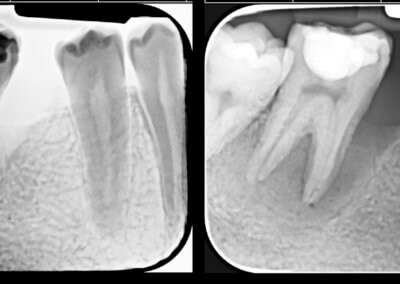

Endodonția este o ramură esențială a stomatologiei, axată pe diagnosticarea, prevenirea și tratamentul afecțiunilor pulpei dentare și a țesuturilor periapicale. Această specialitate joacă un rol crucial în salvarea dinților naturali, evitând extracțiile și menținând sănătatea orală pe termen lung. Prin tehnici avansate și echipamente de ultimă generație, endodonția asigură tratamente precise și eficiente, contribuind la redarea sănătății și funcționalității dinților într-un mod durabil și predictibil.